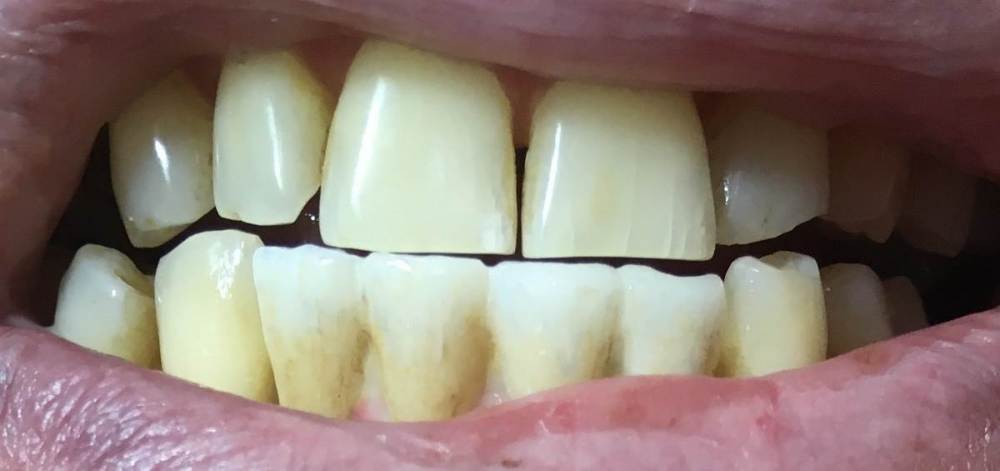

Здравствуйте, 10 месяцев назад установил мостовидную коронку на двух имплантантах. Первые 4-5 месяцев коронки сидели плотно, а потом стал замечать, что появился люфт  вперед-назад, а потом и небольшой люфт в вертикальном, осевом направлении, когда легонько потянешь. Обратился к врачу который ставил,  он сделал снимок сказал, что всё нормально. Спустя два месяца я отправил два письма с просьбой назначить другого врача и разобраться - тишина. Еще через месяц, обратился к другому врачу в туже клинику и  описал проблему. Врач сказал что это нормально , такое мол случается винты ослабли. сейчас подтянем. Но начав откручивать понял, что затяжка соответствует и винты сидят плотно. Значит, говорит - мешает десна, запишу вас к хирургу он вокруг импланта подрежет и коронка сядет, а ещё говорит, может зуб мешает, тогда его обточим.

Вот еще фото сразу как сняли коронку 07.07.23 , хорошо что снял.730312457_.thumb.jpg.ca4d73e258835ccdac5df35cc02cd34f.jpg1440661631_1.thumb.jpg.02d3c625a1074bce1c61f0ae06aa1f7d.jpg